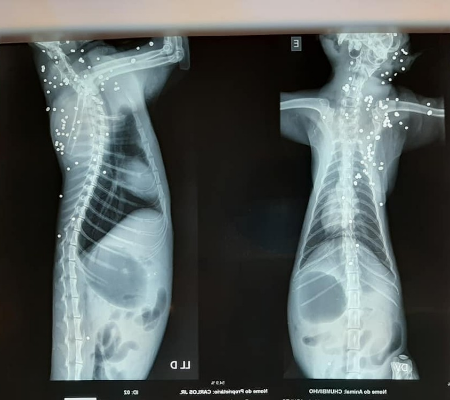

Um gato precisou ser resgatado após ser encontrado com mais de 100 perfurações causadas por disparos de arma de fogo, em São José do Rio Preto (SP). Mesmo recebendo atendimento veterinário por dois dias, o animal não resistiu aos ferimentos e morreu nesta sexta-feira (6). As informações são do G1.

“Eu conversei com uma pessoa que entende. Acreditamos que foi um tiro disparado com uma cartucheira. Tinham mais de 100 projéteis no corpo do animal”, diz o veterinário.